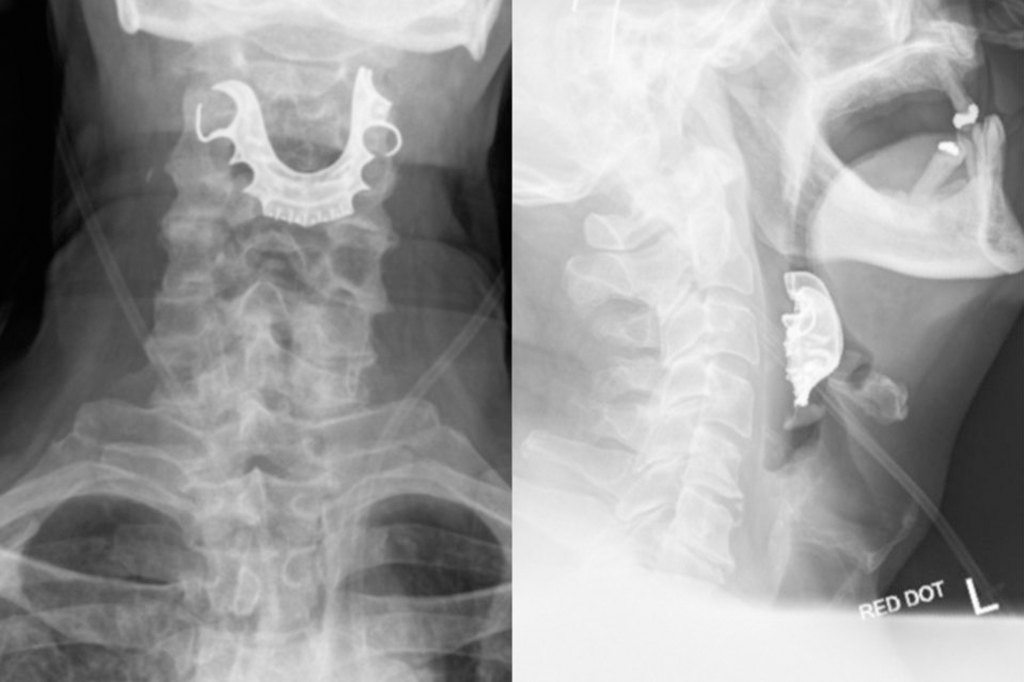

Idoso engoliu sua dentadura durante cirurgia – e ela entalou na garganta